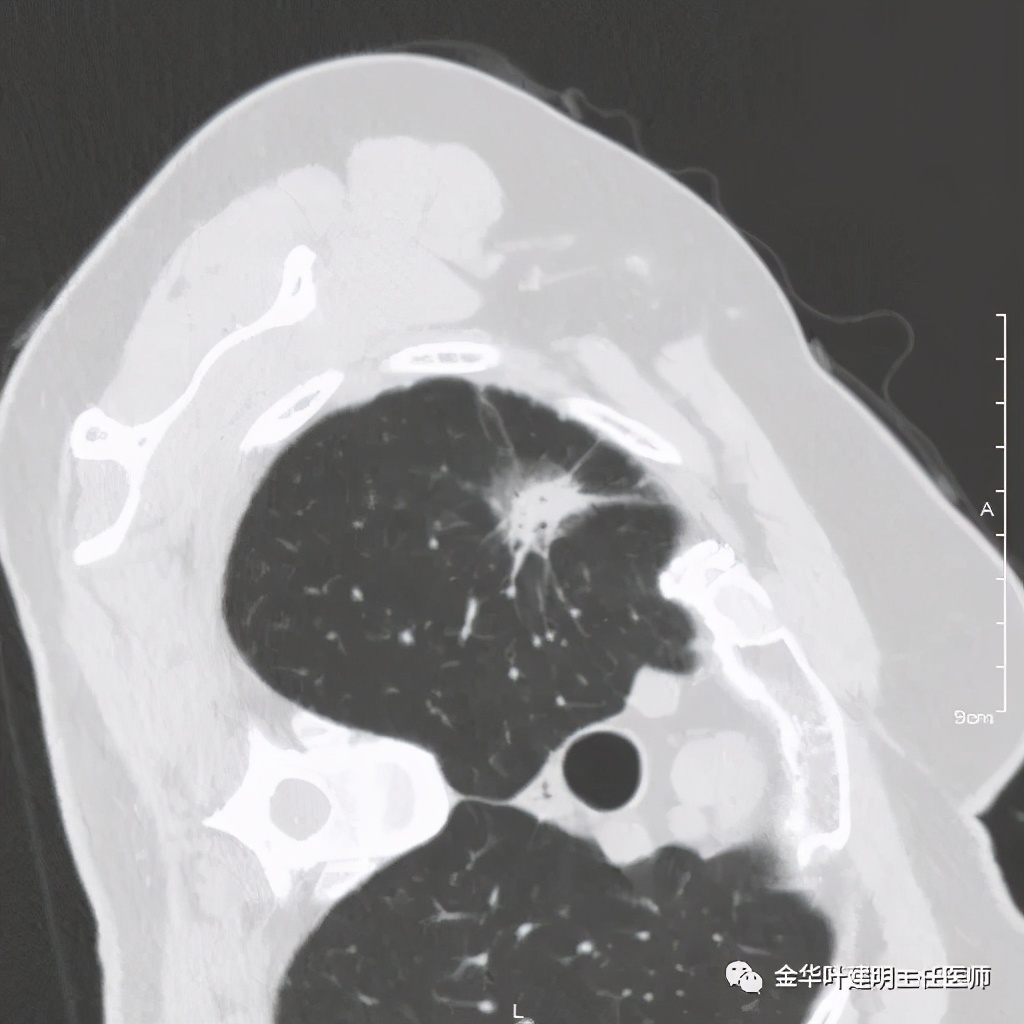

五、浸润性腺癌之粘液腺癌:

影像特征:这个病例是我在术前仅凭影像就判断其为粘液腺癌,术后确诊的。粘液腺癌表现为 实性乏收缩力、密度较均匀 的实性结节。病灶的边界一般非常清楚,没有毛刺、磨玻璃、卫星灶等,但又乏收缩力,像本例紧贴胸膜也不会有牵拉凹陷;同时病灶的密度又比较均匀(粘液成份)。良性肿瘤密度要更高些、慢性炎没有这么光整的边界,也容易有瘢痕收缩方面的影像表现、其他实性的腺癌则要有收缩力、腺泡型虽然也缺乏收缩力,但密度要不均匀些。